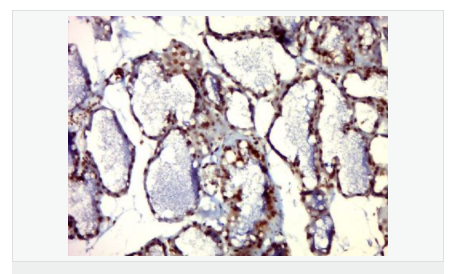

| 产品应用 | WB=1:500-2000 ELISA=1:5000-10000 IHC-P=1:100-500 IHC-F=1:100-500 IF=1:100-500 (石蜡切片需做抗原修复) not yet tested in other applications. optimal dilutions/concentrations should be determined by the end user. |